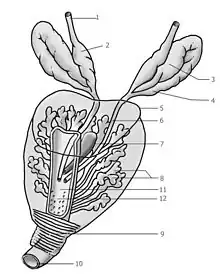

Le cancer de la prostate est un cancer fréquent touchant la prostate, une glande de l'appareil reproducteur de l'homme. Le cancer se développe à partir des tissus de la prostate quand des cellules y mutent et se multiplient de façon incontrôlée. Celles-ci peuvent ensuite s'étendre (se métastaser) en migrant de la prostate jusqu'à d'autres parties du corps, particulièrement les os et les ganglions lymphatiques du pelvis.

Le cancer entreprend la portion périphérique de la glande, au contraire de l'hypertrophie prostatique bénigne qui intéresse la zone centrale, périurétrale.

Chirurgie

Elle repose sur la prostatectomie, dite radicale ou totale. Elle consiste en l'ablation de la prostate et des vésicules séminales et peut être précédée d'un prélèvement des ganglions de drainage de la prostate. La chirurgie peut être réalisée par voie ouverte (incision chirurgicale au niveau de l'abdomen ou au niveau du périnée), par voie cœlioscopique abdominale, ou bien à l'aide de l'appareil Da Vinci ; la chirurgie est réservée aux cancers localisés à la prostate et offre de grandes chances de guérison si le cancer est effectivement localisé et peu ou moyennement agressif (agressivité estimée par le score de Gleason) ; elle peut entraîner une incontinence urinaire, le plus souvent temporaire et des troubles de l'érection. Il n'y a pas de supériorité d'une technique par rapport à une autre en ce qui concerne les résultats carcinologiques et les résultats fonctionnels urinaires et sexuels.